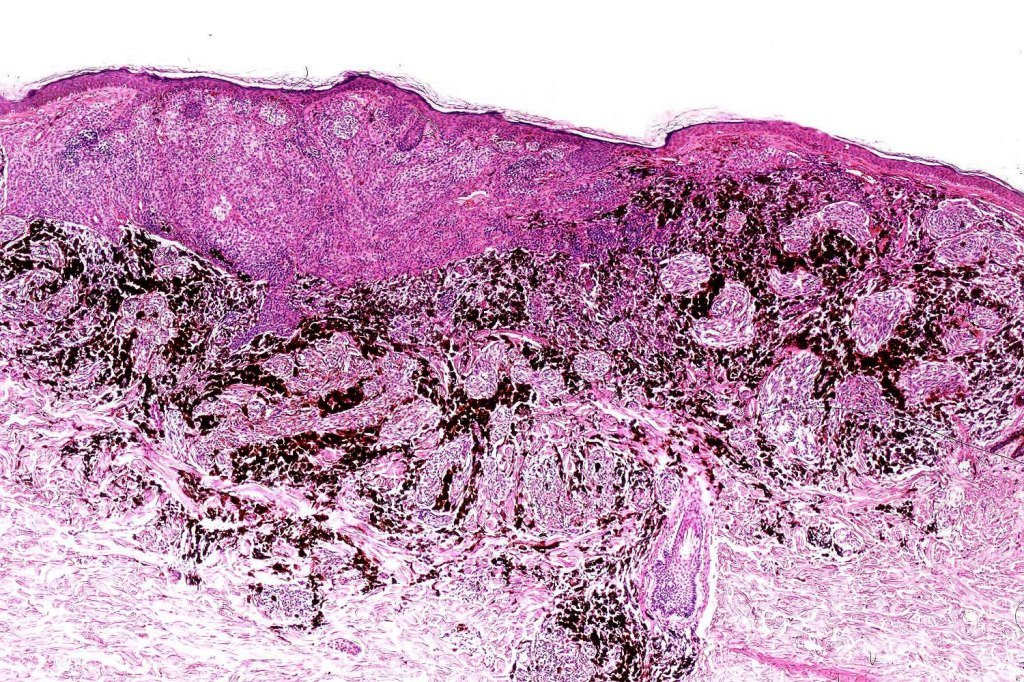

Combined common & deep penetrating nevus